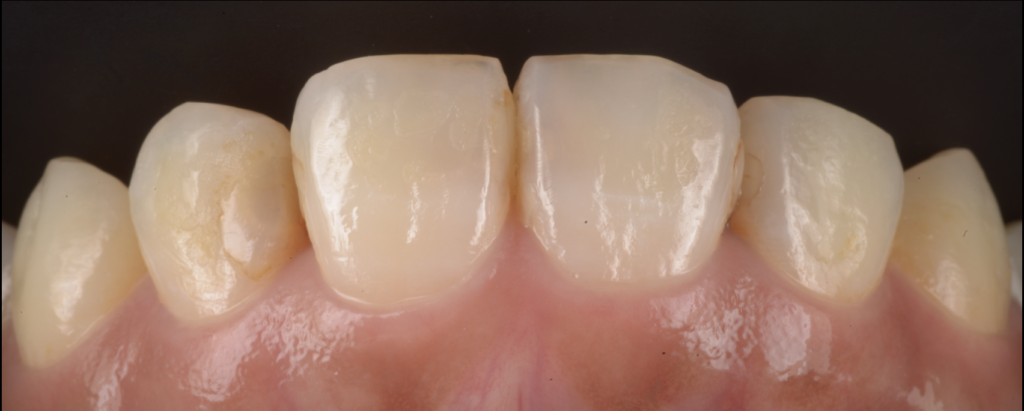

【池袋の症例】主訴:前歯の色/「虫歯があると言われた」

今回の患者さんは、上顎前歯部について

- 「前歯の色が気になる」

- 「虫歯があると言われた」という不安を抱えて来院されました。

前歯は目につきやすく、少しの着色でも気になります。

ただし、ここで重要なのは「見た目の色=虫歯」とは限らないこと、そして「色だけ」と決めつけるのも危険だということです。

なぜなら、接着が壊れている場合、見た目の変色の奥で感染が進んでいることがあるからです。

初診時に疑うポイント

- 修復物の辺縁に着色(マージンステイン)

- 詰め物が浮いて見える、段差が疑われる

- 見た目よりも内部で進行している可能性

今回も、色の違和感をきっかけに精査し、修復物を外してみると、想定以上に内部で感染が広がっていました。

つまり、「色が気になった」という主訴は、結果的に歯を守るための重要なサインだったといえます。